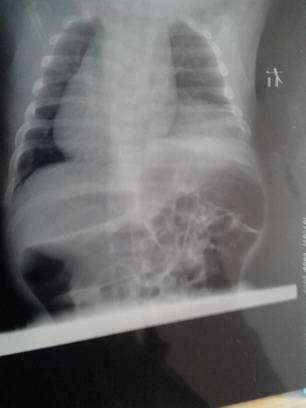

病情分析: 您好!从图片上看,宝宝的膈肌膨升还是很明显的,确实需要手术治疗,否则长时间会造成宝宝心脏尤其是右侧肺功能异常,受限,造成宝宝的缺氧等情况。任何手术都是有风险的,大夫会把风险降到最低的。 指导意见: 1、建议暂时观察,定期复查,遵医嘱择期给宝宝手术治疗。 2、费用与您选择的医院,采取的手术...方式、有无合并症等都有着直接的关系。 祝宝宝早日康复!